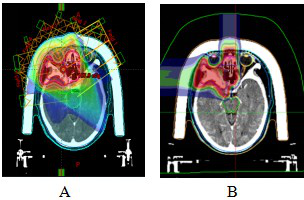

Case 3: Female, 59 years old, postoperative right orbital ACC. She underwent ‘right orbital mass excision + orbital repair’ at West China Hospital of Sichuan University in April 2023, and her postoperative examination showed that she had ACC. she was admitted to our hospital one month after the operation, and now she has obvious limitations in eyelid closure, right eye external rotation and downward rotation. After a thorough examination and evaluation of the patient, the patient was treated with CIRT on 12 June 2023, with one prescribed dose of PTVboost: 15Gy (RBE)/5fx. the second prescribed dose was PTV: 54Gy (RBE)/18fx, and the total tumour dose amounted to 69Gy (RBE)/23fx, with the dose distribution shown in Fig. 7. the CIRT and VMAT plans, under the premise that both meet the prescription requirements, the typical comparison of dose distribution in axial images, the surrounding normal tissue CIRT plan is significantly smaller than the VMAT plan low-dose irradiation range, see Figure 8.The efficacy of CIRT treatment was compared by imaging data before and after treatment, and the patient's efficacy was assessed according to the RECIST1.1 criteria for evaluating the effectiveness of tumour efficacy, which reached a partial remission (PR), see Figure 9. During CIRT treatment and within 1 month after treatment, the patient experienced grade 1 radioskin injury, and no adverse events greater than grade 2 were observed. As of July 2024, the patient is currently surviving with tumour and continues to be followed up in the long term.

Figure 8 VMAT plan and carbon ion plan dose distribution in orbital ACC patients

Note: Figure 8A: VMAT plan dose distribution n orbital ACC patients. Figure 8B: Carbon ion plan dose distribution n orbital ACC patients.